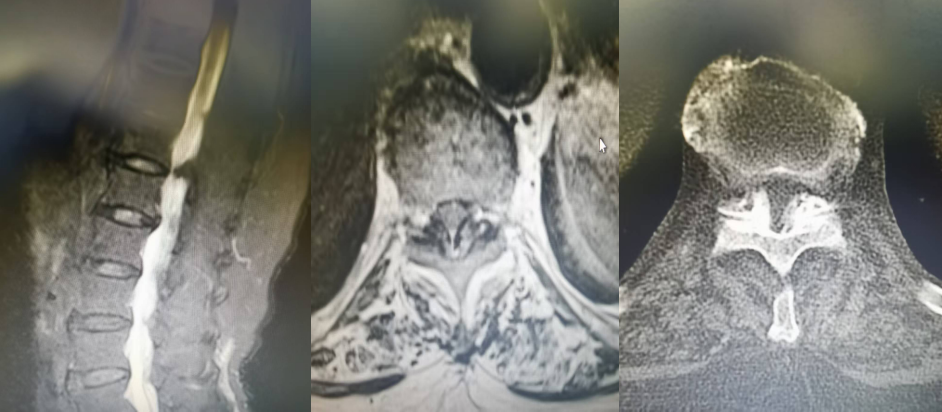

T10/11黃韌帶鈣化,椎管狹窄,硬膜囊受壓嚴(yán)重,腦脊液不通暢

患者術(shù)后復(fù)查CT及MRI均顯示脊髓無明顯受壓,腦脊液通暢,術(shù)后患者下肢肌力級感覺明顯恢復(fù),已能下地行走